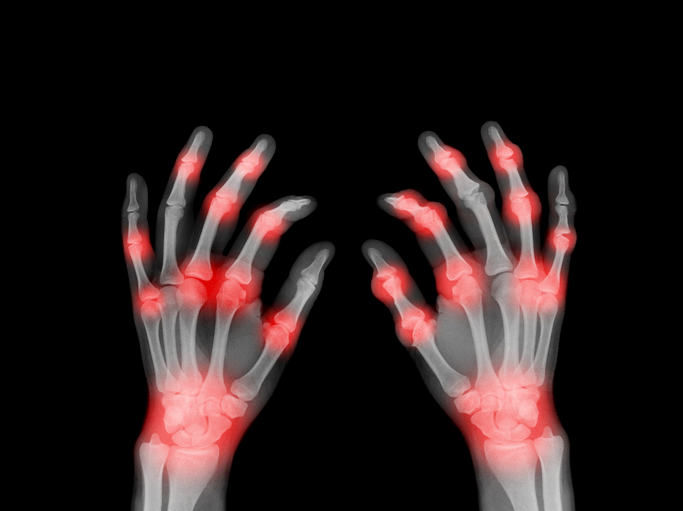

류마티스 관절염은 체내의 면역 시스템이 잘못하여 정상적인 조직을 공격하는 자가면역 질환의 일종입니다. 이로 인해 관절 주변의 조직에 염증이 발생하고, 장기적으로는 관절의 변형과 손상을 초래하게 됩니다. 이 질환은 특히 손가락, 손목, 무릎, 발목 등의 작은 관절에 영향을 주며, 복합적인 증상을 동반합니다.

류마티스 관절염은 다양한 증상을 가지고 있습니다. 주로 관절의 통증, 부종, 강직성을 동반하며, 이러한 증상은 대개 양측의 동일한 관절에서 발생합니다. 일반적으로 아침에 증상이 가장 심하며, 몇 시간 동안 더 지속될 수 있습니다.

이외에도 피로, 체중 감소, 발열 등 일반적인 증상이 동반될 수 있습니다.